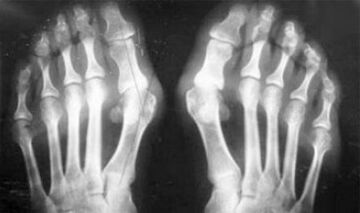

The difference between arthritis and osteoarthritis of the fingers and the hands of the hands is that the first disease is cured and the second does not.With arthritis, the synovial housing and the articulation capsule are touched.

The defeat of the cartilage and bone tissue occurs only in the last stages in a careless state.With osteoarthritis, the cartilage tissue is affected first, and then the bone, the inflammation of the synovial membrane is of secondary origin, that is, it develops against its background.

- Joint deformation occurs;

- The articulation is deformed, its mobility decreases.